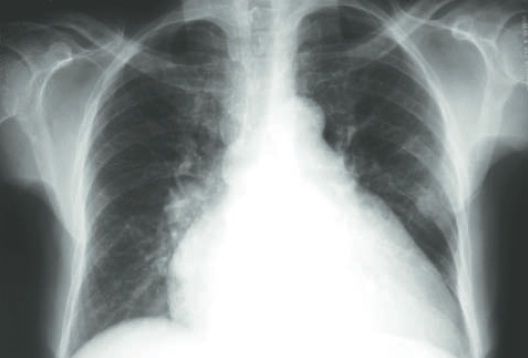

2. ICC

1. Edema MMII

1. Dispneia

1. Palpitação

1. Astenia

2. Doença de Chagas

1. Sintomas de ICC

1. Cardiomegalia

1. Menor capacidade de contração

1. Taquicardia ventricular